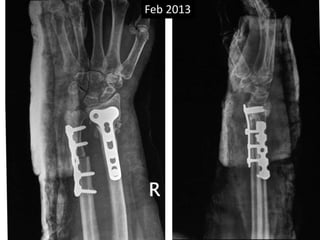

Feb 2013

April 2014

Sept 2013

Surgery • Volarexposure • Removal of scar tissue and clearing of bone ends. • Release of soft tissue contractures. • Shortening of ulna and plating. • Plating of radius with bone grafting.